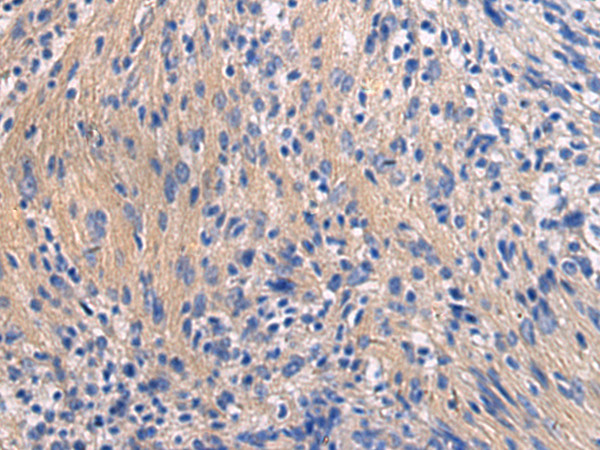

分类: 科研抗体货号: P13460别名: LGP1; D11LGP1应用: IHC反应种属: Human